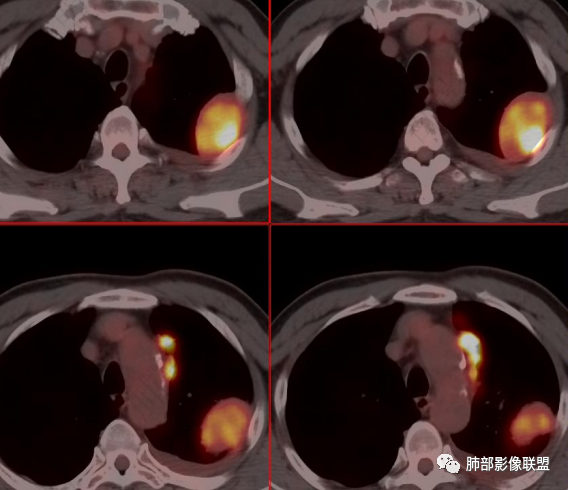

【每日晨读】PET-CT示左侧胸膜区多发高摄取的结节及肿块影,会是罕见病吗?

放射小白: 老年男性,左侧上后胸廓胸膜下团块状占位,左侧膈肌脚可见软组织密度影,纵隔可见淋巴结影,左侧胸腔可见少量积液;左侧胸膜下病变、左侧膈肌病变、纵隔、肺门多发高FDG摄取,首先考虑胸膜间皮瘤,鉴别SFT、转移瘤。

秦化君: 左侧胸腔积液伴胸膜局限增厚及多发大小不等结节影,核素浓聚。考虑间皮瘤,鉴别转移瘤。

宇宙: 左上胸膜肿块、左侧胸膜多发结节及左侧膈肌增厚,高摄取,左侧胸腔少量积液,胃窦壁增厚,肝内低密度灶,贫血,考虑转移瘤,鉴别间皮瘤。

丽: 老年男性,左肺上叶胸膜下,纵隔胸膜及左侧脊柱旁见多发软组织密度影,边界光滑清晰,胸膜下脂肪间隙消失,临近骨质无破坏,高摄取,左侧胸腔积液,考虑间皮瘤,鉴别转移瘤

放射线 (王秀仙): 左侧胸膜、纵隔内见多发结节及团块状异常高摄取,左侧胸腔积液,肝内多发类圆形低密度,胸椎左侧异常软组织肿块,考虑转移可能,胸膜间皮瘤?

尘缘: 老年男性,黑便伴腹胀两月,肿标除铁蛋白外,其他都不高,胸膜多发高摄取结节伴胸椎旁结节。诊断常规要考虑恶性,主要有三个可能,1、恶性间皮瘤,以胸膜多发结节改变为主伴胸椎旁转移结节,腹部未见明确高摄取,所以这个可能有。黑便可能只是普通胃或十二指肠溃疡引起,需要胃肠镜明确。2、腹部消化道肿瘤伴胸膜及胸椎转移,有黑便两月伴腹痛,要考虑,但腹部没有高摄取原发灶,肿标不高,所以这个可能小。3、淋巴瘤,胃肠道表现就诊,但胃肠道无相关高摄取,肝脾也无明显肿大,无发热,可能不大。除了恶性外,还必须考虑:髓外造血,理由:患者便血二月,贫血明显,椎旁与胸膜旁多发结节摄取一致。疑惑的是髓外造血是否可以这样高摄取?综上:考虑恶性间皮瘤>髓外造血>转移。

段建民: 患者老年男性,消化道出血来住院,胸部CT提示双侧胸膜多发结节,PET-CT提示高摄取状态,定位胸膜上,胸膜的纵隔侧和胸壁侧及食管旁的淋巴结均有高代谢,肺内未见明显肿块和占位的表现。考虑淋巴瘤?间皮瘤?